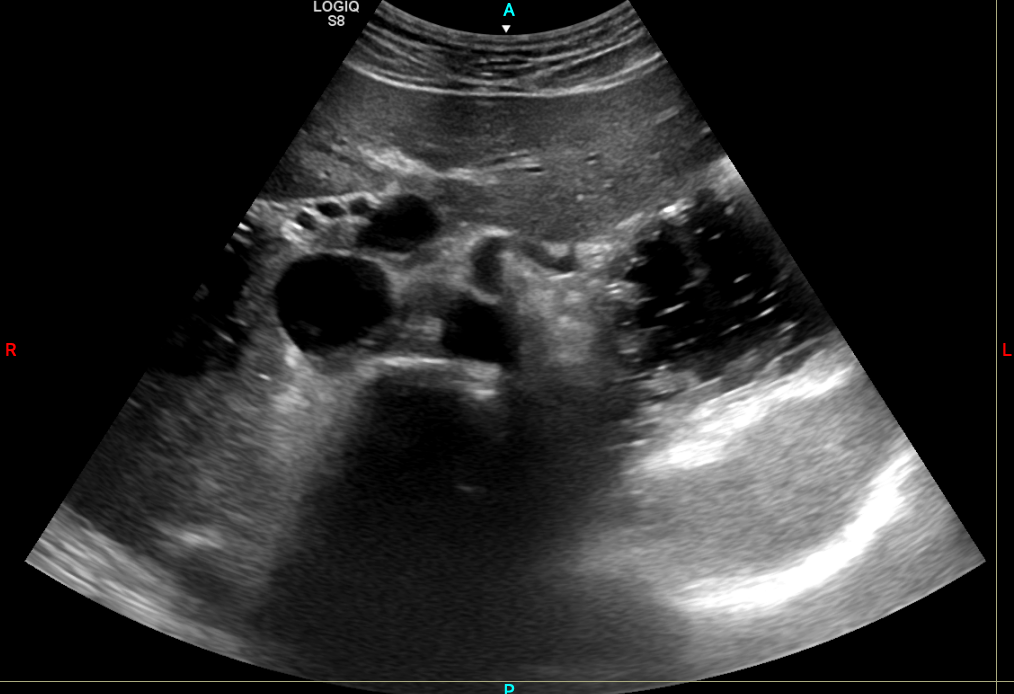

Corte axial subxifoideo mostrando sombra acústica posterior a la aorta abdominal

Figura 1: Aprecia en este corte axial subxifoideo, como posterior a la aorta abdominal, se aprecia una sombra ...